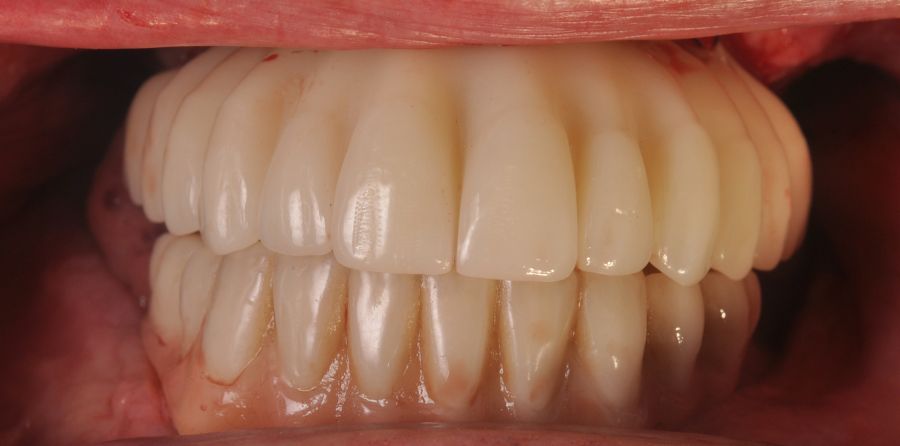

The surgical procedure was performed under general anaesthesia and nasotracheal intubation. A supracrestal incision and detachment of a maxillary flap of total thickness was made (Figures 9 and 10). The boundaries of the dissection were both infraorbital ridges, both laterally malar bodies and the anterior half of the hard palate caudally. In addition, a customized cutting guide was used so that the SI was completely in direct contact with the bone (Figure 11) and the mesh was fixed with the different 1.5 mm osteosynthesis screws in the nasal and zygomatic buttresses (KLS Martin, Freiburg, Germany) (Figure 12). The closure was performed with nonresorbable suture. Finally, the PMMA provisional rehabilitation was screwed for the immediate load, with a torque of 20 N on the implants (Figures 13-15).

Two months later, with the soft tissues healed around the connections (Figure 16), a new intraoral scanning was made of the implants and the provisional prosthesis for future restoration. A FRI type passivity test (rigid impression splint) was manufactured with an aluminium structure to assess the correct fit on the implants (Figure 17). For implant-supported rehabilitation, a sintered structure was made in chrome-cobalt with machined bases covered with acrylic resin teeth from Bredent® (Figures 18-21).